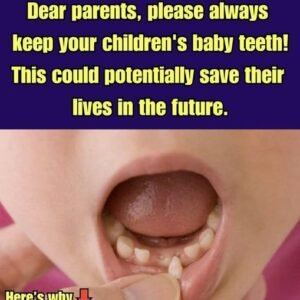

Attention, Parents! You Might Want To Hold On To Your Kids’ Baby Teeth

Cryopreservation of stem cells may sound like science fiction, but I assure you, it is not. According to scientists, baby teeth have stem cells that help regenerate various…